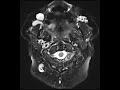

Venous Malformations

These images show multiple T2 hyperintense extracranial lesions involving the right periorbital soft tissues, right buccal region abutting the right facial vein, and in the left masticator space anterior to the masseter. The lesion in the right periorbital soft tissues shows a fluid level and minimal nodular venous enhancement inferiorly. The lesion anterior to the left masseter muscle shows two rounded signal voids corresponding to calcifications see on a CT not pictured here which are compatible with phleboliths. Time of flight imaging shows no evidence of arterial supply to these lesions. Findings are most compatible with multiple venous malformations with phleboliths being a characteristic feature. Venous malformations of the head and neck may be transpatial or localized and are most commonly found in the buccal region as seen on the right in this patient with additional common sites including the submandibular and masticator spaces.